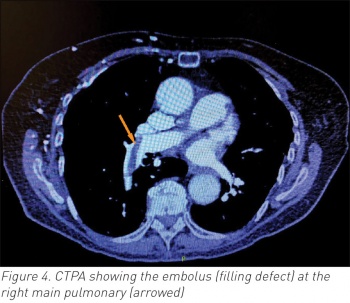

The underlying PE wasn’t diagnosed when she developed AF. She received timely anticoagulation based on already diagnosed subacute deep vein thrombosis (DVT) and her CT pulmonary angiography (CTPA) subsequently confirmed acute embolus in the right main pulmonary artery. Her AF responded well to beta-blocking therapy. The source was right lower limb DVT. Without AF, her PE would have passed unnoticed. The treatment course would have changed acutely if patient had become unstable, but fortunately this wasn’t the case. This case highlights the possible dilemma of treating acute rapid AF that wasn’t primary but rather secondary to an underlying PE.